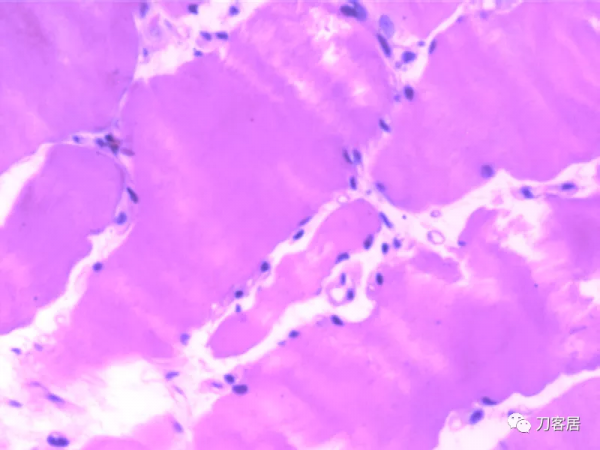

患者發病後右腿腓腸肌病理切片所見:灰紅色至綠豆大組織四塊。光鏡檢查結果:病理診斷“右側腓腸肌”肌纖維肥大變性,個別肌纖維可見溶解及空泡。患者家屬拒絕屍檢。

(6)病理學檢查右側腓腸肌肌纖維粗細不均,肌細胞漿溶解,縱橫紋不清晰,有纖維肥大變性,個別肌纖維可見溶解及空泡。根據以上特點,此患者可診斷MH。

患者發病後(右腿腓腸肌)